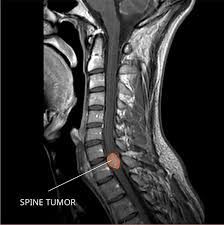

Ependymoma is a type of tumor that can form in the brain or spinal cord. Ependymoma begins in the ependymal cells in the brain and spinal cord that line the passageways where the fluid (cerebrospinal fluid) that nourishes your brain flows. Ependymoma can occur at any age, but most often occurs in young children.